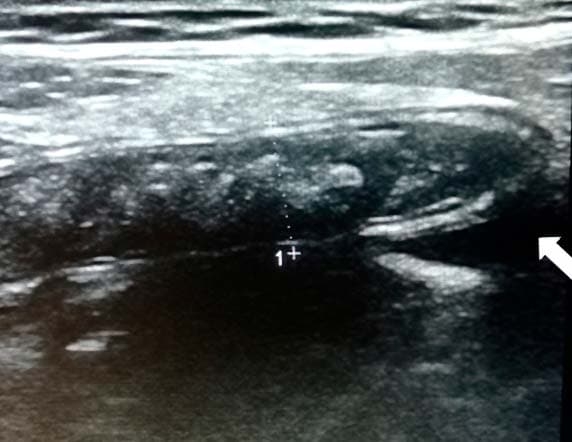

Рисунок 9. Картина УЗИ при гангренозном аппендиците.Из протокола УЗИ: «В правой подвздошной области визуализируется слепо заканчивающийся, не перистальтирующий участок кишки 10 мм в диаметре, болезненный при компрессии датчиком; в просвете жидкость и каловые камни» (см. рис. 9).

Из протокола операции: «Аппендикс резко утолщен, напряжен, грязно-серого цвета, покрыт фибрином». Диагноз после операции: гангренозный аппендицит (см. рис. 10).